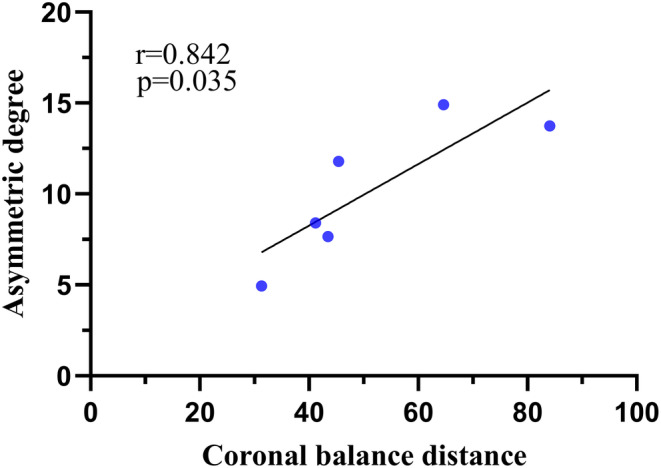

The asymmetric degree (AD) in the change of the multifidus was significantly higher at the apex of both the main and fractional curves compared to the erector spinae (Z = ‐4.839, p < 0.05; Z = ‐2.695, p < 0.05). The change in AD of the erector spinae was weakly positively correlated with the AVR (0 < rs <1, p < 0.05), while that of MS was weakly negatively correlated with TLK in Type A (−1 < rs <0, p < 0.05) (Fig. 4). The change in AD of the erector spinae was strongly positively correlated with CBD at the apex of the main curve in Type B (0 < r < 1, p < 0.05) (Fig. 5). At the apex of the fractional curve, the change in AD of the erector spinae was strongly positively correlated with CBD (0 < rs <1, p < 0.05), and the change in AD of the multifidus was strongly positively correlated with AVR (0 < rs <1, p < 0.05), while it was strongly negatively correlated with PI and SS (−1 < r < 0, p < 0.05) in Type C (Fig. 6).